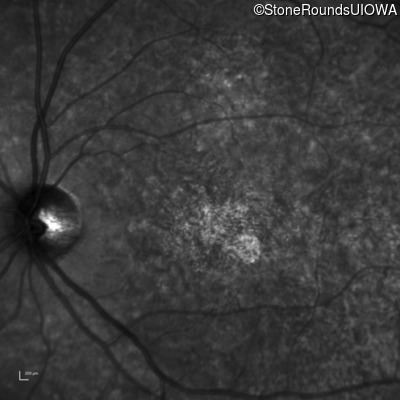

The clinical features favoring the diagnosis of ABCA4-associated autosomal recessive Stargardt disease in this patient include: loss of acuity at the beginning of the second decade, parafoveal photoreceptor loss on OCT, pisciform flecks in the macula with clear peripapillary sparing, and normally sighted parents.

All three of the cardinal ophthalmic features of Mendelian macular dystrophies are present in this patient. The most striking features of the fundus exam are the numerous yellow flecks at the level of the RPE. Flecks are most commonly seen in AR Stargardt disease and pattern dystrophy although they may be seen in some of the rarer Mendelian maculopathies as well. The visual acuity in patients with AR Stargardt disease is often "worse than the fundus looks" while the acuity in pattern dystrophy is often quite good despite extensive flecks. The pedigree of this patient is compatible with ABCA4-associated Stargardt disease and the better than expected acuity is attributable to foveal sparing (see below). The onset of reduced acuity at age 10 is much more characteristic of ABCA4 disease than pattern dystrophy. Another feature present in this patient that is very frequently seen in Stargardt disease is peripapillary sparing. However, this sign can be seen in pattern dystrophy as well. When central atrophy is present in ABCA4-associated Stargardt disease it often somewhat shiny (which is uncommon with the geographic atrophy of pattern dystrophy or age-related macular degeneration). Some patients with ABCA4-associated Stargardt disease can have some preservation of the fovea giving a zonal "bullseye" appearance to the center of the macula. Sometimes this preservation is associated with preserved acuity as in this case. The outer nuclear layer (ONL) is much thinner than normal on OCT, indicative of photoreceptor loss. This is associated with a thinning of the ellipsoid zone which is usually many times brighter and thicker than the external limiting membrane (ELM). These two lines are essentially equal in intensity in this patient. The foveal sparing is seen on OCT only as a small bit of retinal convexity in the center of the atrophy coupled with a small bit of residual RPE flanked by bare Bruch's membrane. The presence of a robust I2e isopter on Goldmann perimetry places this patient in the least severe half of all Stargardt patients (see Schindler, et al., 2010). Most patients with ABCA4-associated disease are somewhat myopic as is this patient. Stargardt patients also tend to perform very poorly on pseudoisochromatic plates, even when their acuity is still fairly good as it is here.